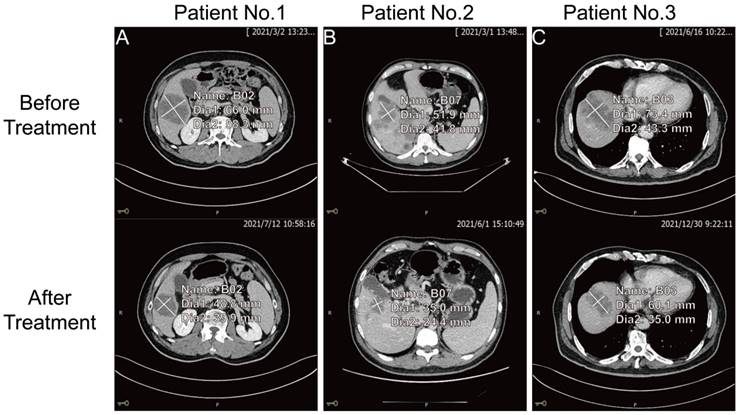

The key to making a correct treatment plan is to monitor and judge the efficacy of chemotherapy in patients with distant metastatic CRCs. By evaluating the treatment response, 14 distant metastatic CRCs reached PR, and the remaining CRCs were classified as non-PR (including CRCs evaluated as PD or SD on chemotherapy). Apparent decrease of tumor size was observed at the site of liver metastasis from colorectal cancer (n=3) after three chemotherapy treatments in the PR group (Figure 4). Our follow-up test found that the serum CDH3 level in the PR group gradually decreased with the increase of numbers of chemotherapy sessions, which was not observed in non-PR. CA 24-2, CA 19-9, CA 72-4, and CEA in the PR group also showed a decrease in overall chemotherapy, while strong fluctuations were noted in the levels of these biomarkers in the non-PR group (Figures 5 and 6). However, no significant differences were observed in the serum levels of these markers between PR group and non-PR group after chemotherapy, except for CDH3 (Table 4).

Figure 4

The comparison of tumor size at the site of liver metastasis from colorectal cancer before and after three chemotherapy treatments for three patients in the PR group.

J Cancer Image